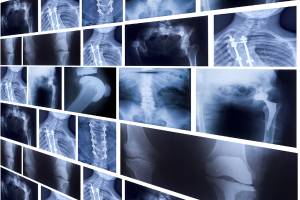

At Al Naas Medical Lab, we are committed to providing patients with advanced diagnostic solutions that combine accuracy, safety, and comfort. Among our specialized services, X-Ray and Barium Meal tests play a vital role in detecting and diagnosing various health conditions.

X-Rays are one of the most common and effective imaging tools in modern medicine. With the help of high-resolution imaging technology, our X-Ray services allow doctors to examine bones, joints, and internal organs. They are especially useful in detecting:

At Al Naas Medical Lab, we ensure each X-Ray is conducted safely, using equipment designed to minimize radiation exposure while delivering clear and precise images.